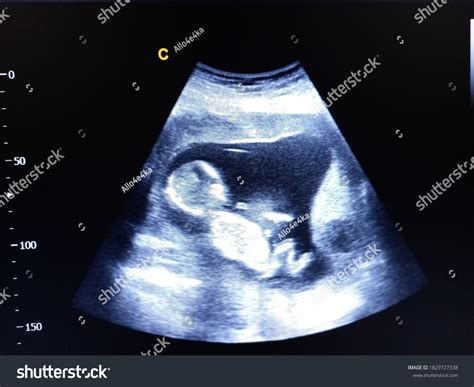

A 14 week ultrasound is typically performed between 13 weeks and 14 weeks of pregnancy. It is often referred to as the “nuchal translucency” scan because it measures the thickness of fluid behind the baby’s neck. This measurement, along with other factors, can help assess the risk of certain chromosomal abnormalities, such as Down syndrome.

During the 14 week ultrasound, you will lie on an examination table with your abdomen exposed. The technician will apply a gel to your belly and use a transducer to capture images of your baby. The procedure is painless and usually takes about 20-30 minutes.

The technician will look for several key features, including:

• Baby’s Heartbeat: The heartbeat should be clearly visible and audible.

• Nuchal Translucency: The thickness of the fluid behind the baby’s neck will be measured.

• Baby’s Anatomy: The technician will check for the presence of all major organs and structures.

• Placenta and Amniotic Fluid: The position of the placenta and the amount of amniotic fluid will be assessed.

Heartbeat The baby’s heartbeat should be strong and regular, usually between 120 and 160 beats per minute.

Nuchal Translucency This measurement helps assess the risk of chromosomal abnormalities. A thicker measurement may indicate a higher risk.

Anatomy The technician will check for the presence of all major organs, including the brain, heart, stomach, and kidneys.

Placenta The position of the placenta will be noted to ensure it is not covering the cervix, which could lead to complications later in pregnancy.

Amniotic Fluid The amount of amniotic fluid will be assessed to ensure it is within normal ranges.